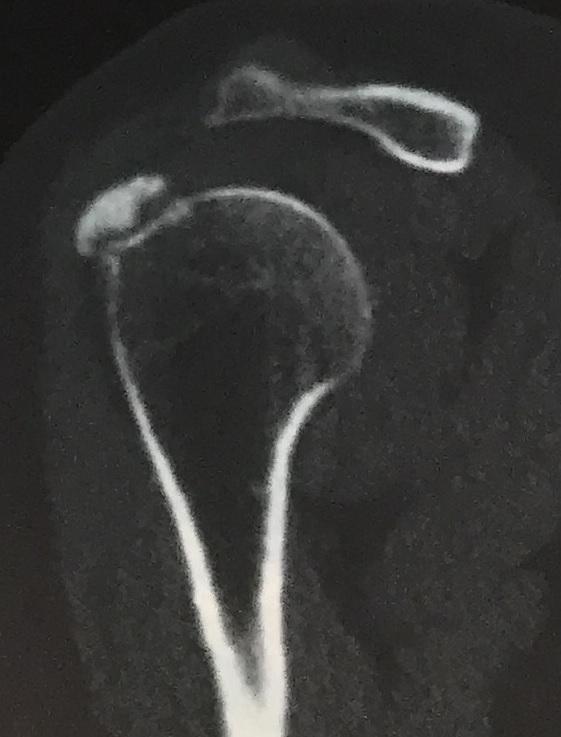

Een 58-jarige vrouw bezoekt de polikliniek Orthopedie met pijn in de rechter schouder. Hoewel zij al langere tijd schouderklachten heeft, is de pijn fors toegenomen na een val op haar schouder twee weken eerder. Zij is hiervoor in het buitenland behandeld, maar blijft pijn houden.